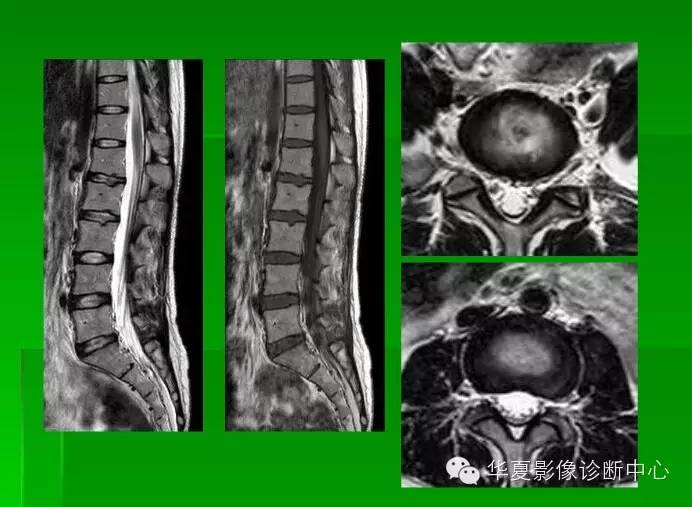

椎间盘发育退变与病变mri表现